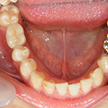

14. インプラント歯冠セット時下顎面観

右下6番部インプラントにセラミック冠を装着(ほとんどの症例では仮着)した下顎写真です。

15. インプラント歯冠セット時右側面観

右下6番部インプラントにセラミック冠を仮着したところです。何とか歯頚部の連続性が保てました。又歯冠乳頭も少し温存できました。キャンセルが多く苦労しましたが、今後は確実に定期健診を受けて下さらないと保障できませんよ。何かあれば、いつでも相談してください。